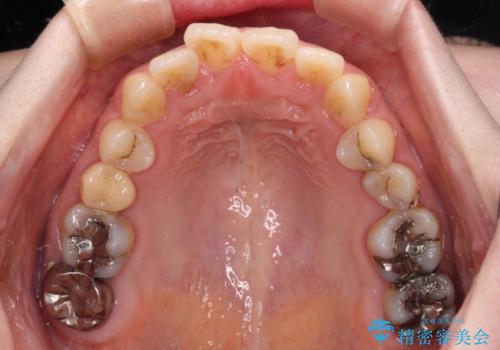

- 捻れた前歯が飛び出しており、口が閉じにくいとのことで来院された患者様です。

出っ歯というわけではないものの、前歯の捻転により口唇が押し出されている状態でした。

親知らずを抜去し、歯列全体を後方に移動させつつ、IPR(歯と歯の間を削る)でスペースを獲得し、インビザラインを用いて叢生を解消しながら前歯の突出を改善することとしました。